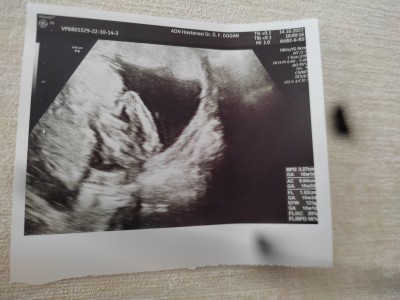

Cinsiyet tahmini yapar mısın 15+4

Cinsiyet tahmininde bulunur musunuz ?

15+4

Tam net değil canım ama sanki bacak arası boş gibi kiz olabilir

Kız mı cinsiyet doktor görmüştür sanırım bacak arası gözüküyor??

Ultrasyonu çok kötü hiç bisey belli olmuyor

Bacak arasi bos prensese benziyor

Gostermis zaten doktor tahminfe bulunmadimi canim. Erkek gibi geldi bana